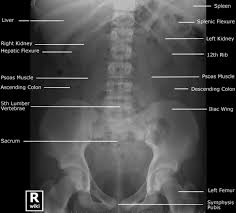

Kidney X Ray Normal. The only exception is patients with acute renal colic. In adults the normal kidney is 10 14 cm long in males and 9 13 cm long in females 3 5 cm wide 3 cm in antero posterior thickness and weighs 150 260 g.

In adults the normal kidney is 10 14 cm long in males and 9 13 cm long in females 3 5 cm wide 3 cm in antero posterior thickness and weighs 150 260 g. The only exception is patients with acute renal colic. Due to the right lobe of the liver the right kidney usually lies slightly lower than the left kidney.

A kidney x ray known as a retrograde pyelography is a test that helps your doctor look at how your urinary system is working and check that the shape and size of your organs are normal.

The presence of calcifications kidney stones in the kidneys or ureters may be noted. In the x ray room the patient must appear on an empty stomach. Your urinary system includes your two kidneys and the bladder the tube that connects each kidney to the bladder ureters and the tube that carries urine from the bladder to the outside urethra. The right kidney measures 10 7 cm and the left kidney measures 12 cm normal.